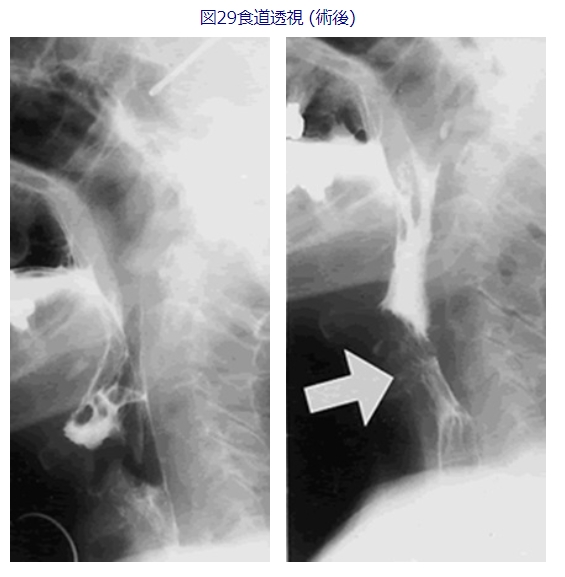

私が幾つかの施設で経験した10例ほどの症例では、頭頸部腫瘍術後の嚥下障害では余り有効ではありませんでしたが、コミュニケーションのとれる脳血管障害には食道入口部の拡張手術がある程度有効でした。図28、29に一例の術前術後の嚥下バリウム像を呈示します。